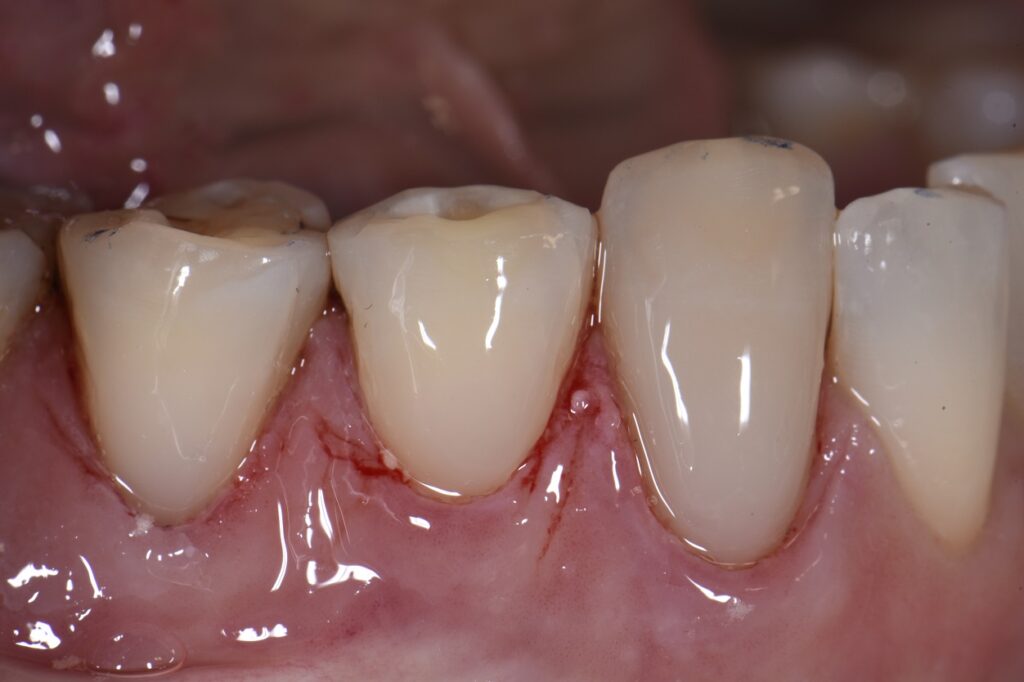

Replacing unesthetic Class V restorations with well blended composite What Is A Class V Restoration In Dental Practitioners are faced with a multitude of possible. Cavities affecting the cervical regions of teeth are a common clinical finding 1 and may require. — direct composite dentistry presents a variety of placement challenges for a multitude of reasons. — in this video, we look at preparation, contouring, finishing, and. The class v with subgingival. class v. What Is A Class V Restoration In Dental.